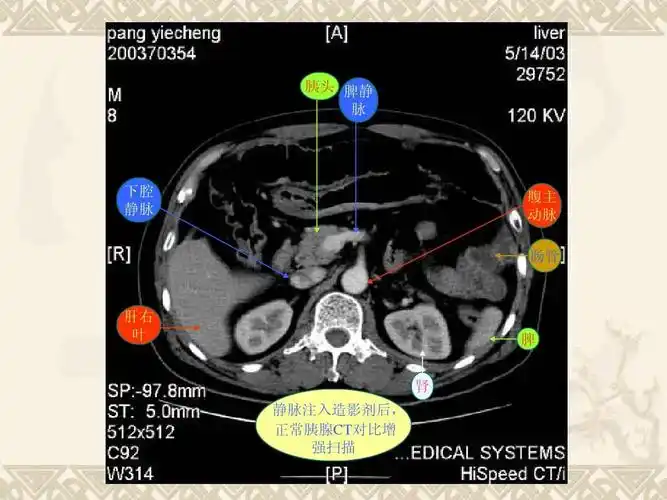

ct平扫胰腺(箭头)从上向下层面分别显示体尾部,颈体和头颈部;b,d,f.